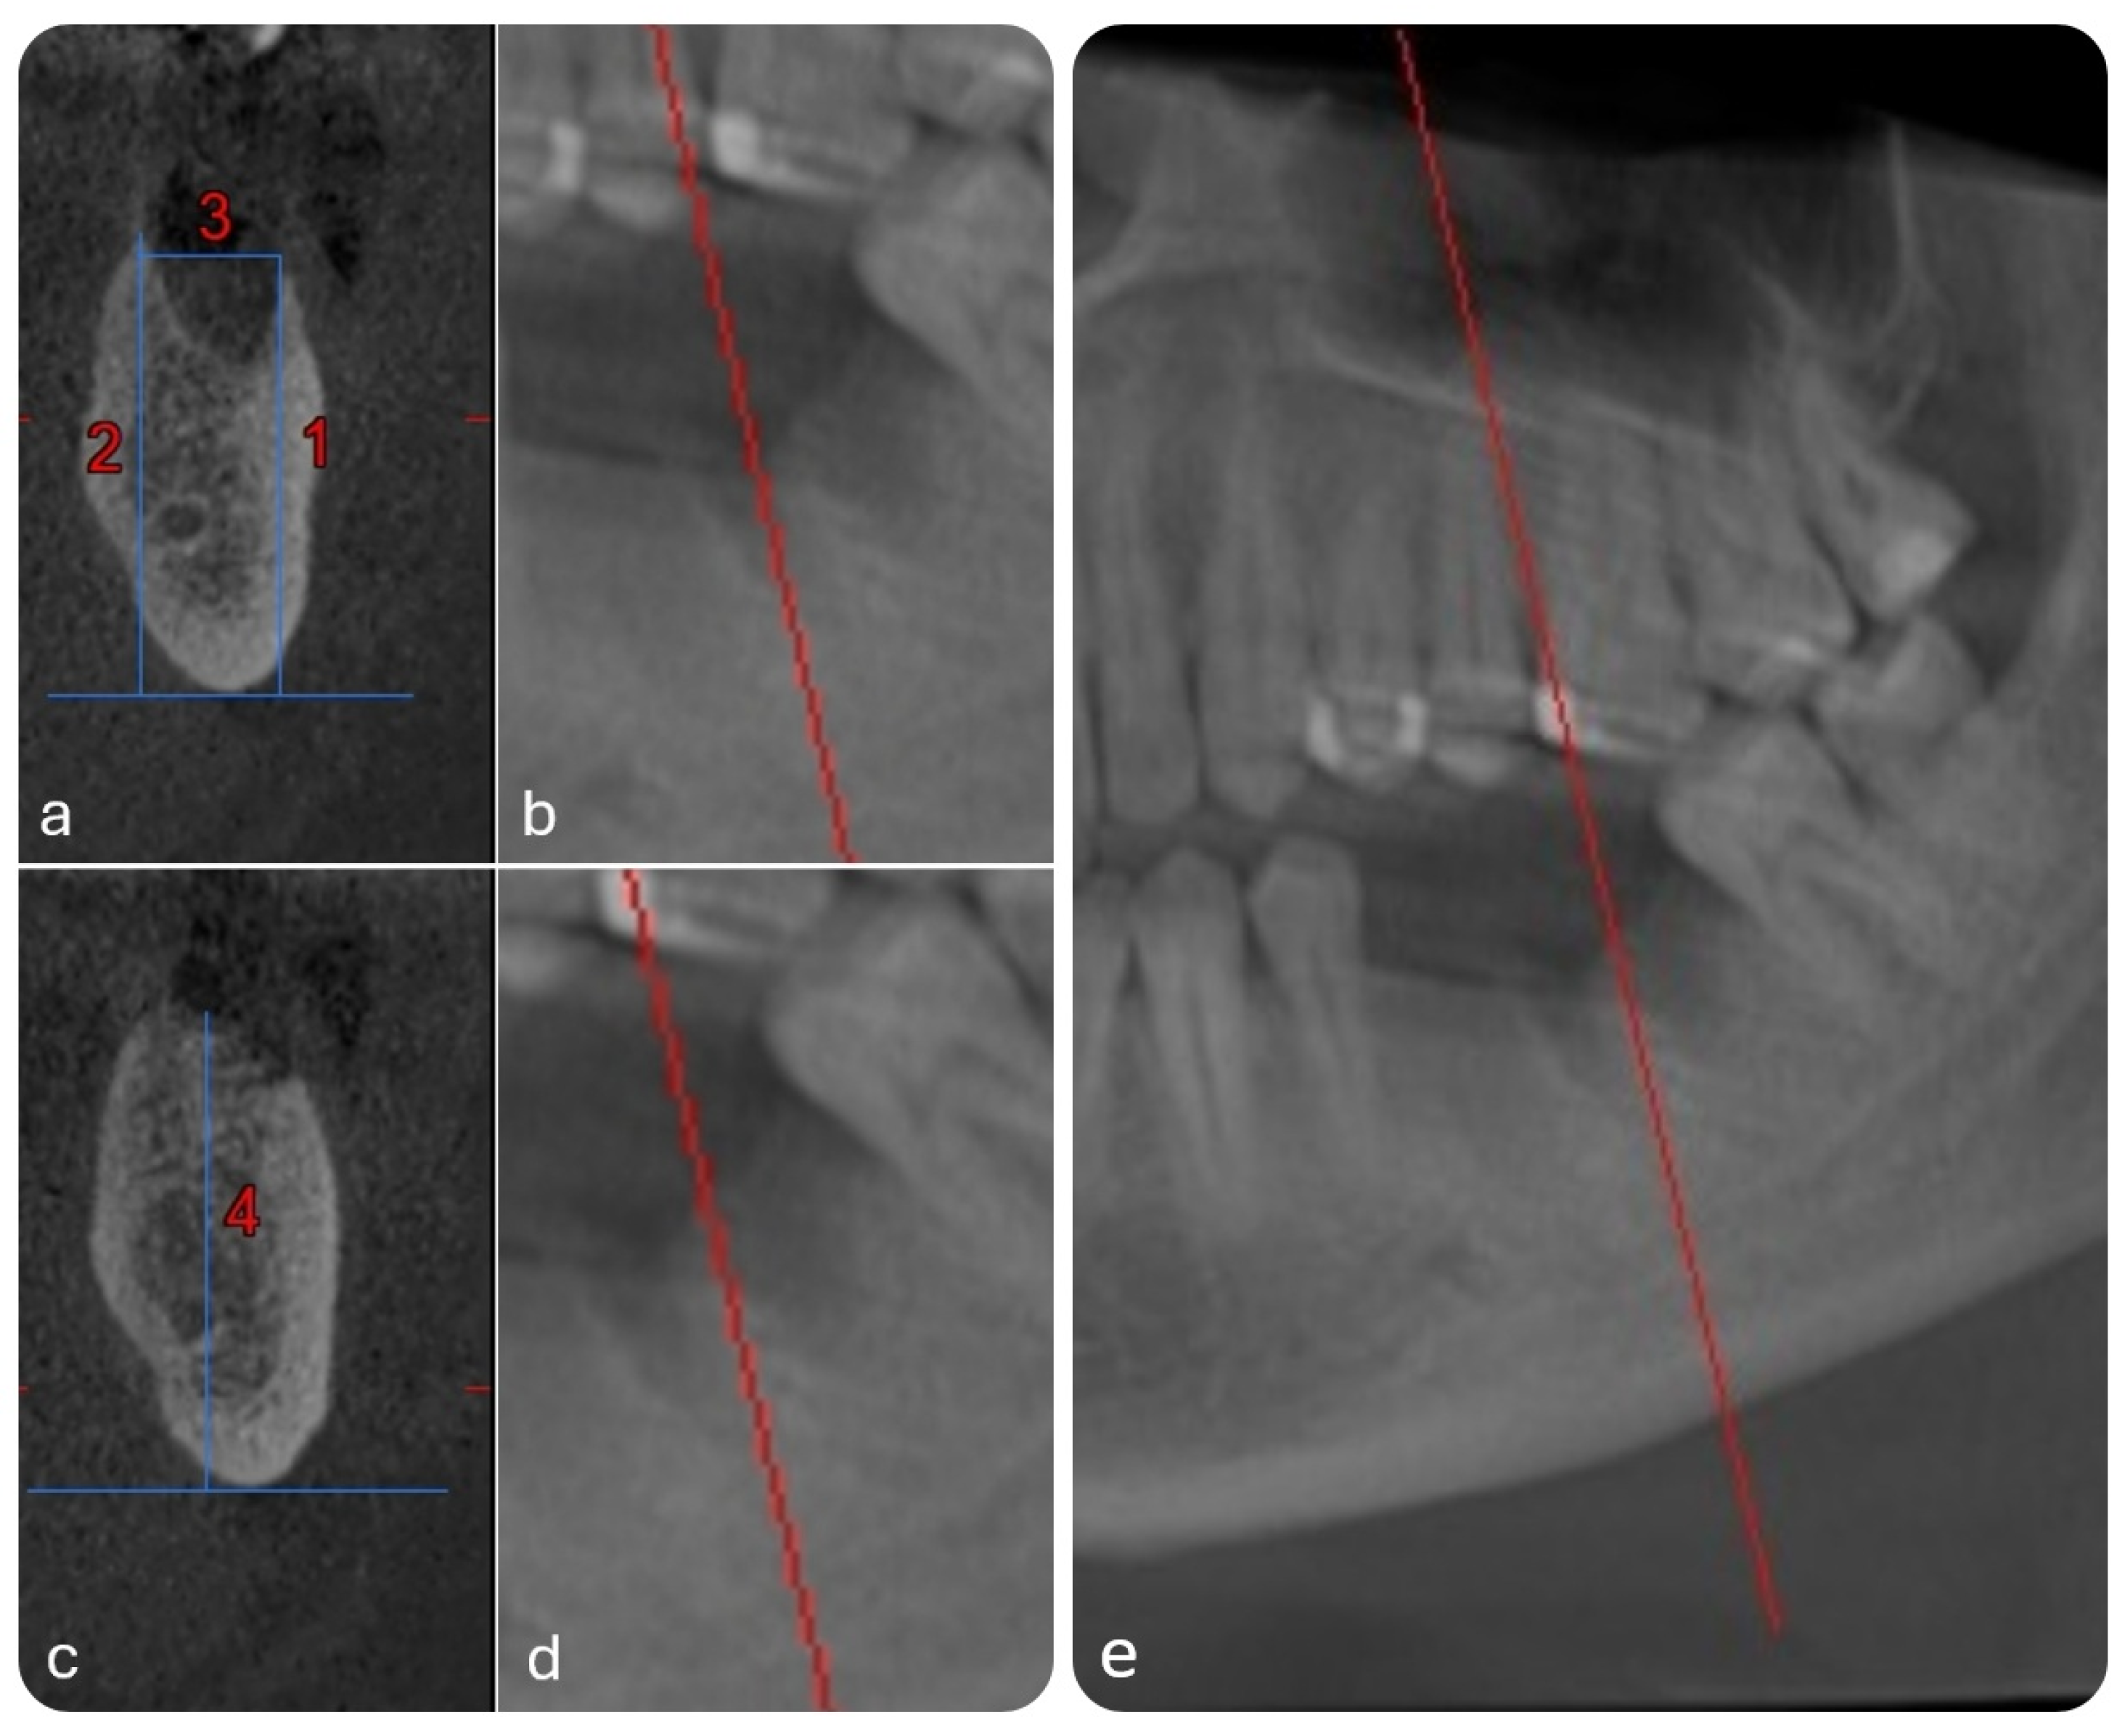

- Buccal bone height (BBH)—distance from the mandibular base to the crest of the buccal alveolar wall (Line 1 in Figure 3a);

- Lingual bone height (LBH)—distance from the mandibular base to the crest of the lingual alveolar wall (Line 2 in Figure 3a);

- Alveolar width (AW)—distance between the buccal and lingual crests (Line 3 in Figure 3a,b);

- Interradicular septum height (ISH)—vertical distance from the mandibular base to the peak of the septum between roots (Line 4 in Figure 3c).